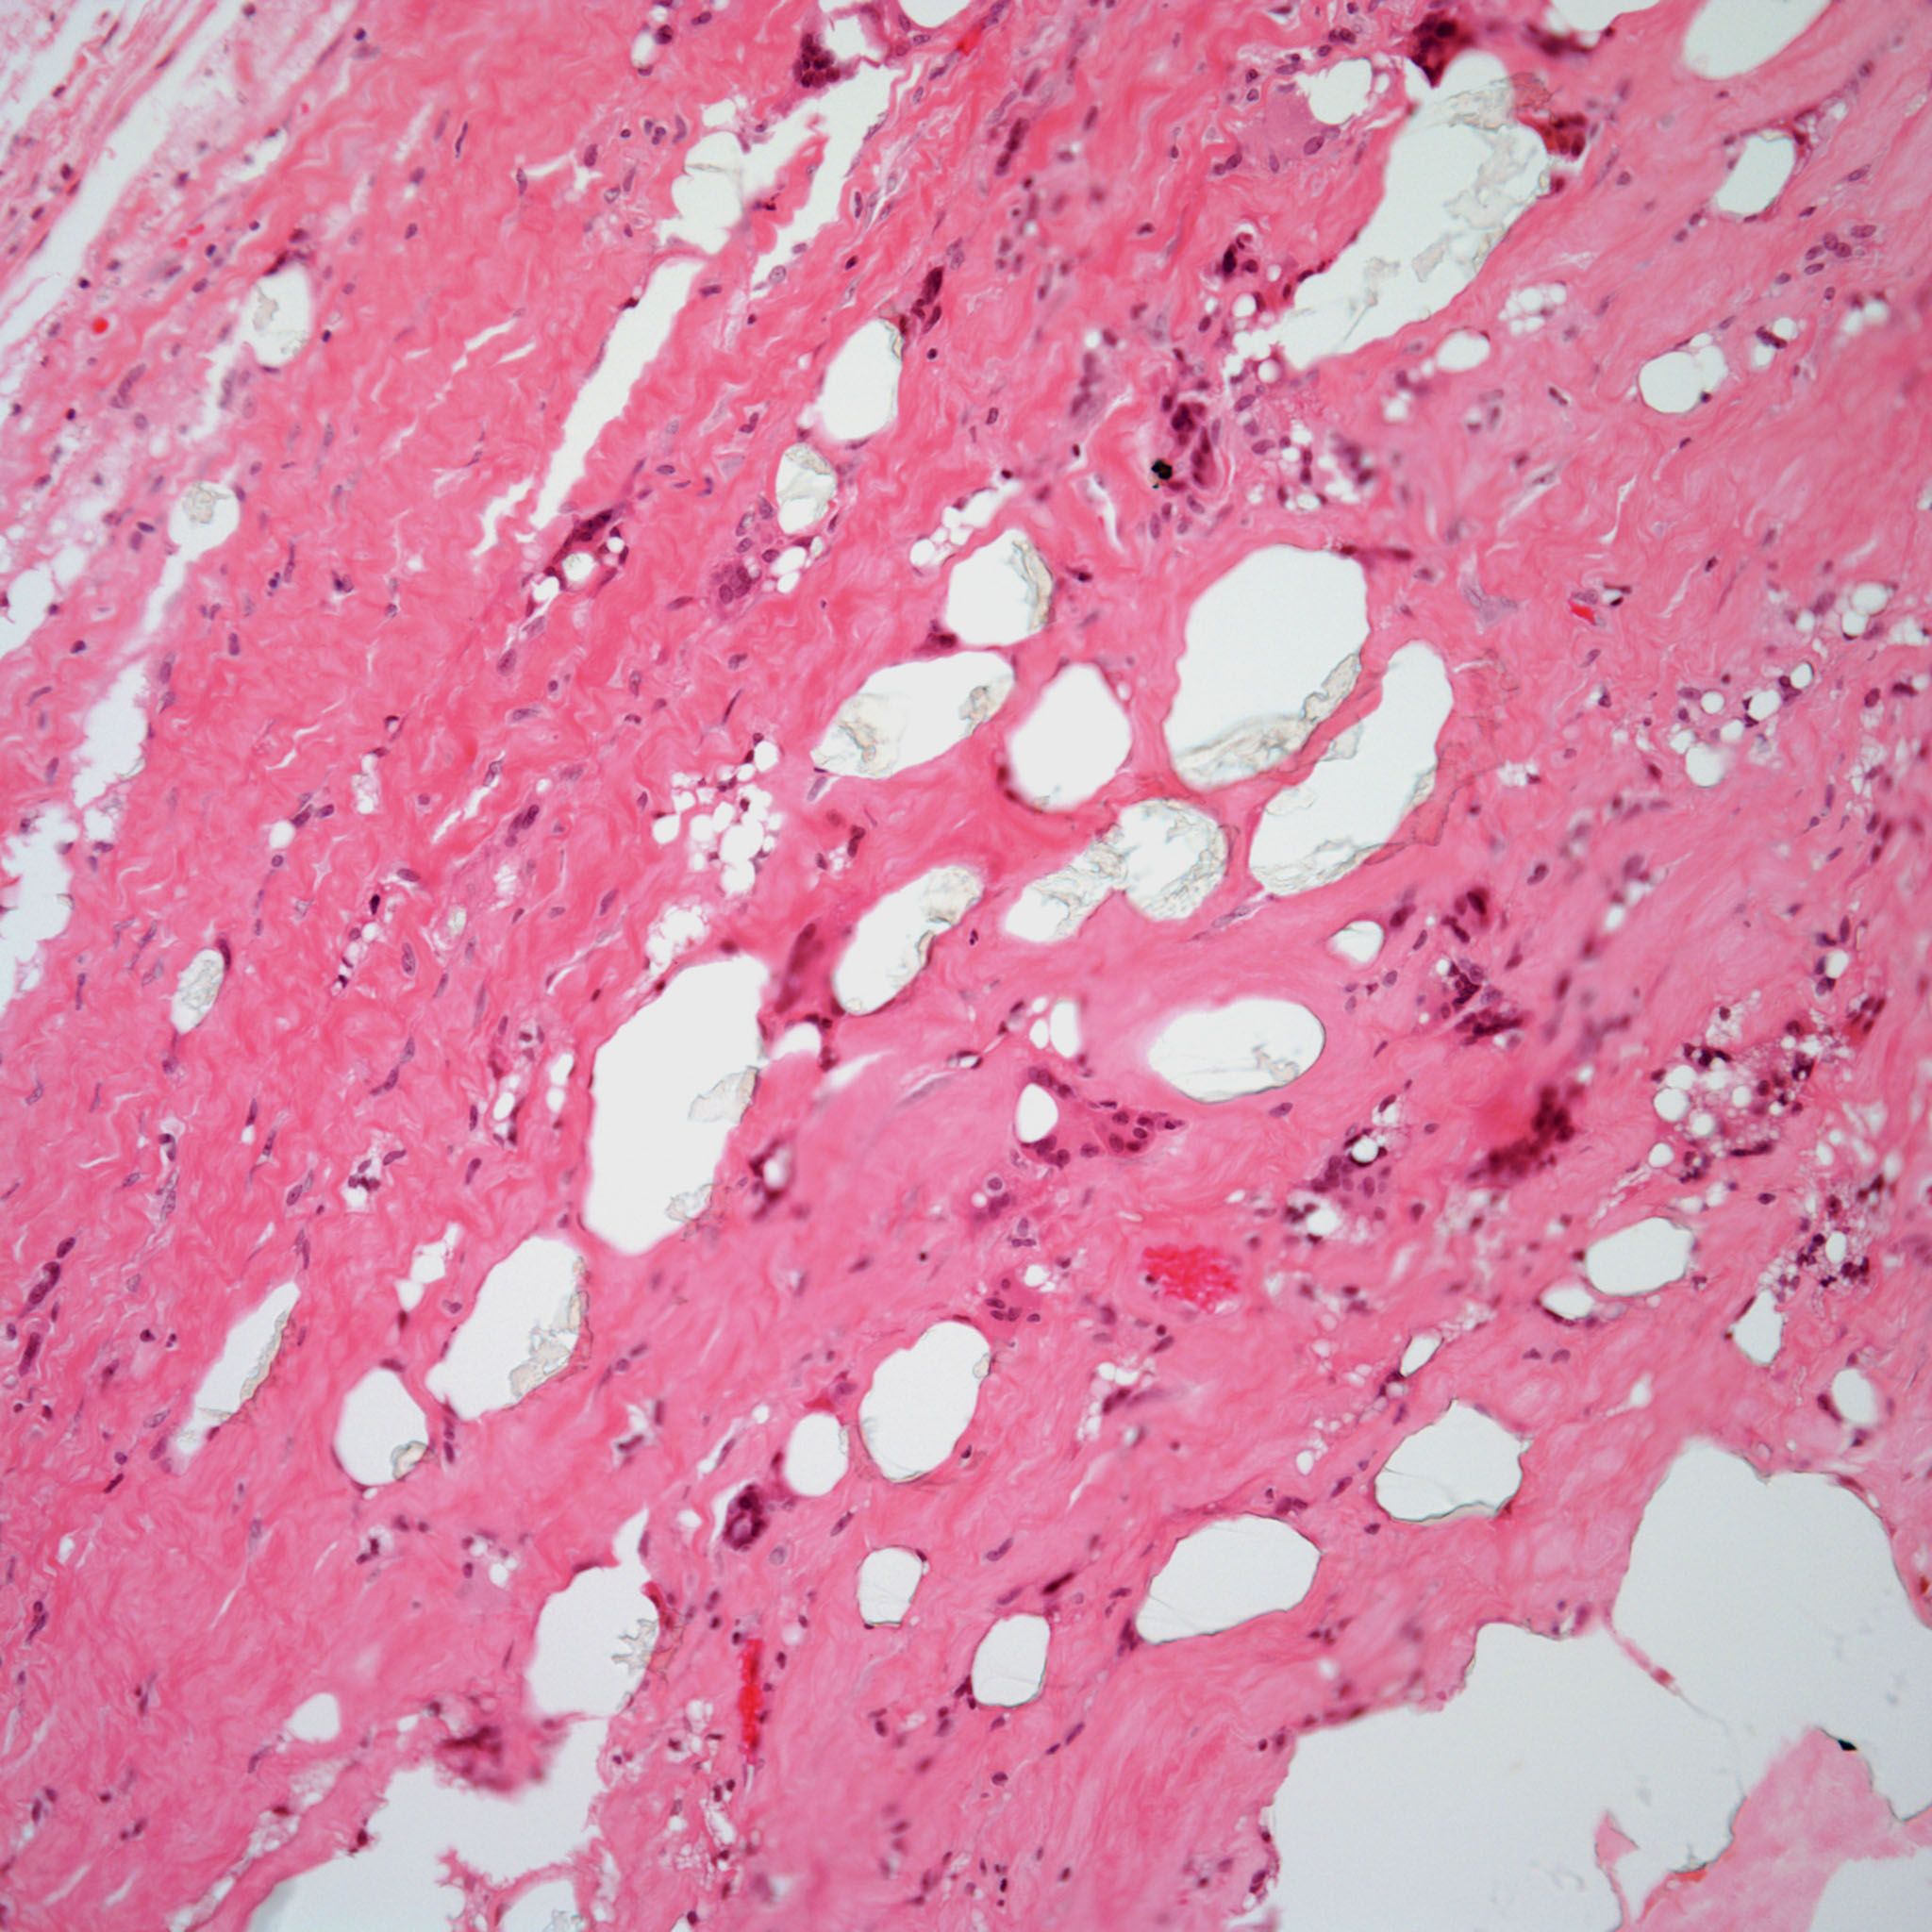

A 32-year-old man presents with pain in the lower back of several weeks’ duration. What is your diagnosis?